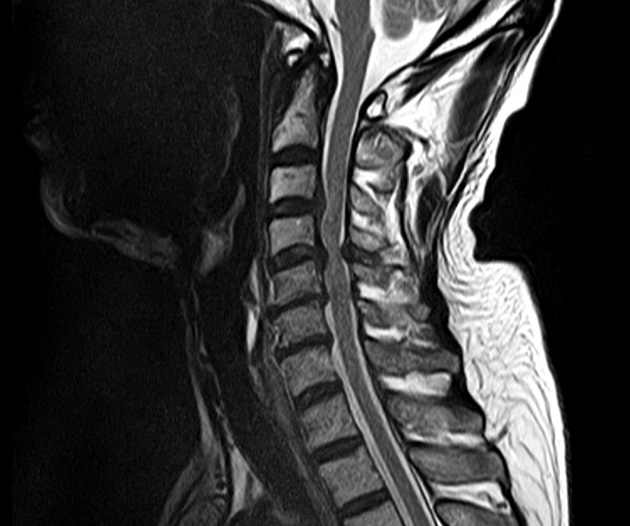

更に、脊椎疾患が原因で生じる手足のしびれ、痛み、歩きにくさなどに対する外科的治療も行っております。

腰部脊柱管狭窄症

頚椎椎弓形成術

【脊椎疾患】腰部脊柱管狭窄症、腰椎ヘルニア、頚椎症、手根管症候群など